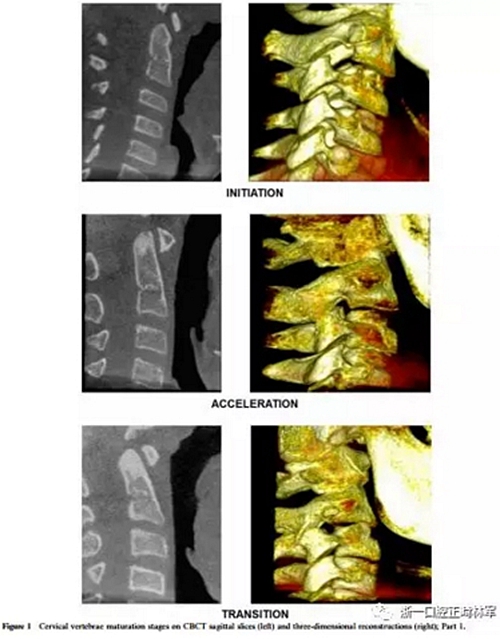

將CBCT三維重建和矢狀切片隨機(jī)分組,并使用軟件OsiriX®(The Osirix Foundation,Geneva,Switzerland)評(píng)估兩次。這些圖像在MacBook Pro(Apple Computer Inc.,Cupertino, CA)。使用OsiriX軟件,通過使用三維成像技術(shù),從醫(yī)學(xué)文件中的數(shù)字成像和通信獲得三維圖像重建。通過多平面重組獲得的矢狀切面是通過將光標(biāo)定位在沿中腭縫線和前鼻棘中心的線上來選擇的。為了避免視疲勞,每天只評(píng)估20幅圖像。評(píng)估分階段進(jìn)行,每次選擇一種展覽模式,第一次和第二次。CBCT圖像在昏暗的房間里,在具有亮度和對(duì)比度恒定特征的屏幕上進(jìn)行解讀,允許利用軟件的縮放,亮度和對(duì)比度工具來增強(qiáng)診斷。每個(gè)展覽模式的圖像解讀最短時(shí)間為15天。在第一次評(píng)估后1個(gè)月,考慮到3D重建和矢狀切片(圖1和圖2),讀片員再次讀片,獲取72條記錄。

椎骨C2,C3和C4的分類方法分為六個(gè)階段,可以描述如下:

1、初期(頸椎成熟指數(shù)-1)

這對(duì)應(yīng)于青春期生長噴發(fā)(PGS)的初始階段,其中預(yù)期有80-100%的增長。椎骨的下邊界是平坦的。在C3和C4的上邊界有一個(gè)從后向前的斜坡。

2、加速期(頸椎成熟指數(shù)-2)

這個(gè)階段接近PGS峰值,預(yù)計(jì)增長率為65-85%。椎骨C2和C3的下邊界呈現(xiàn)一個(gè)小的凹陷,這在C4上仍然是平坦的。 C3和C4的體部呈矩形。

3、過渡期(頸椎成熟指數(shù)-3)

這對(duì)應(yīng)于個(gè)人的高峰增長,預(yù)計(jì)增長25-65%。 C2和C3的邊界呈現(xiàn)出不同的凹陷,這在C4上很微小。椎骨C3和C4的體部是矩形的。